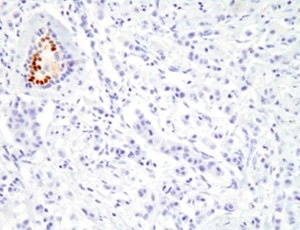

ホルモン療法が効くかどうかは、手術や針生検によって採取した乳がん組織を調べて判断します。